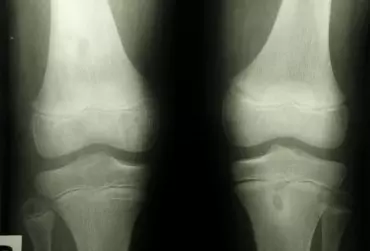

Choroba zwyrodnieniowa stawu kolanowego jest zaburzeniem obejmującym uszkodzenie chrząstki stawowej ze stopniowym niszczeniem macierzy inicjowanej przez mikro- lub makrourazy aktywujące miejscowo przebiegający proces zapalny. W początkowym etapie choroba manifestuje się zmianami na poziomie molekularnym (zaburzenia metabolizmu tkankowego), następnie doprowadza do zmian anatomicznych i fizjologicznych w postaci degradacji chrząstki stawowej, przebudowy kości, formowania osteofitów, stanów zapalnych stawu i utraty prawidłowej funkcji stawu. Typowymi metodami leczenia zmniejszającymi dolegliwości w chorobie zwyrodnieniowej jest farmakoterapia doustna, miejscowa terapia przeciwzapalna, miejscowa suplementacja poprawiająca właściwości lepkosprężyste płynu stawowego hialuronianem sodu, co także zmniejsza tarcie powierzchni stawowych. Ostatecznym rozwiązaniem pozostaje endoprotezoplastyka. Ze względu na przeciwwskazania do stosowania leków doustnych oraz degeneracyjne działanie preparatów sterydowych podawanych miejscowo do stawu kolanowego zaleca się wiskosuplementację jako prewencję bólu. Istnieją liczne badania potwierdzające skuteczność stosowania hialuronianu sodu w dolegliwościach bólowych związanych z chorobą zwyrodnieniową stawu kolanowego.